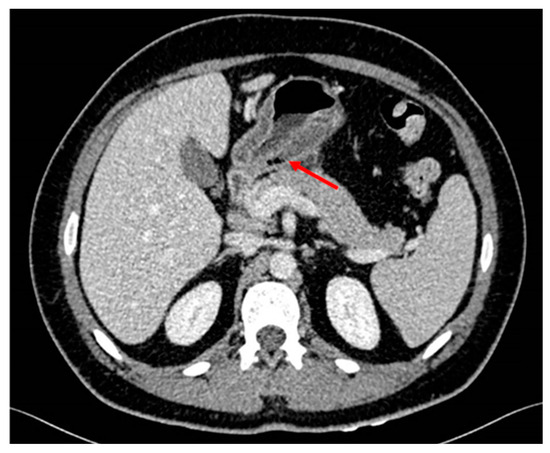

2. Case Description